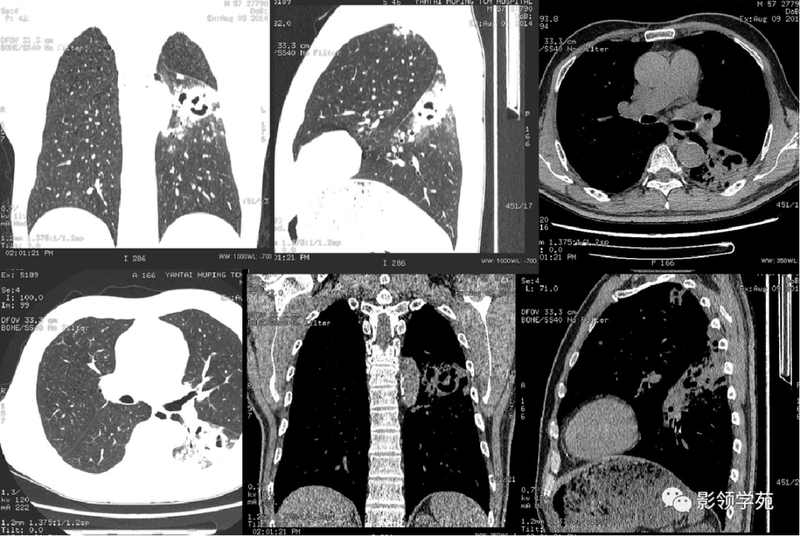

(1)较大含空洞性肿块,洞壁较厚,大于15mm,空洞外壁有分叶、毛刺,洞壁凹凸不平有壁结节,增强可见不规则强化,周围未见明显卫星病灶时,首先考虑周围型肺癌;癌性空洞洞壁一般肺门侧较厚,空洞多偏于外侧,伴有同侧淋巴结肿大更支持肺癌诊断。

(2)空洞病变发生于双肺上叶尖后段、下叶背段,病变周围可见点状、结节状及片状卫星病灶,洞壁组织无明显强化或有包膜线样强化时,考虑结核;结核球的空洞多位于病变的肺门侧,与引流支气管相同,洞内壁一般较光滑。